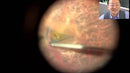

For secure and firm grasping of fine membranes or grasping membranes adherent to the retinal surface. Diamonized for non-slip gripping and improved grasping functionality. Atraumatic blunt tips for gripping perpendicular to the retina. Color code system allows quick and easy identification of the instrument. Stiff and flexible Stainless Steel tube. Anti-glare coating. Easy-to-clean procedure helps to maintain the function of the instrument for a long time. Compatible with Squeeze Handle 12-003T.